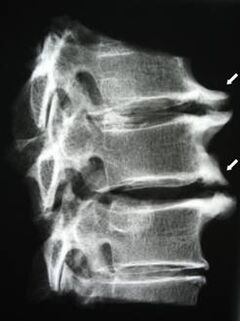

In the initial stages, osteochondrosis is detected using mri.The pathology can then be diagnosed using X-rays.In the X-ray of the cervical spine, a decrease in the distance between the vertebrae, pathological changes in the facet joints and osteophytosis are noticeable.

| Cervical osteochondrosis | The appearance of pathological changes in one or more spinal movement segments.Spinal mobility, development of myofascial pain syndromes and pinching of spinal roots | Cervical pain, paresthesia, and motor disorders spreading to the back of the head and upper limbs.Detection of characteristic changes in the spine in MRI and X-rays |